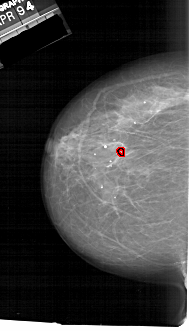

A_1728_1.LEFT_CC

LEFT_CC LINES 6286 PIXELS_PER_LINE 3586 BITS_PER_PIXEL 12 RESOLUTION 43.5 OVERLAY

FILE: A_1728_1.LEFT_CC.OVERLAY

TOTAL_ABNORMALITIES 1

ABNORMALITY 1

LESION_TYPE CALCIFICATION TYPE PLEOMORPHIC DISTRIBUTION CLUSTERED

ASSESSMENT 4

SUBTLETY 2

PATHOLOGY MALIGNANT

TOTAL_OUTLINES 1

BOUNDARY